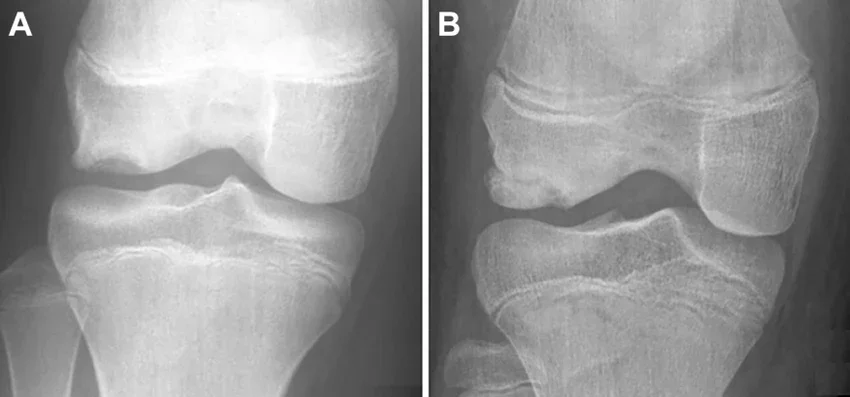

Рентгенографии на дисекиращ остеохондрит на латералния кондил на бедрената кост, изобразяващи вариации в осификацията на дисекираните фрагменти. (A) Неосифициран дисекат, който изглежда прозрачен на рентгенография. (B) Осифициран дисекат с отчетлива граница от увредената кост.

Изображение: researchgate.net/CC BY-NC-ND 4.0

Рентгенологично в началния стадий може да се наблюдава кръгла, с увеличена плътност, субхондрална зона, отделена от нормалната костна структура със склерозен вал. На по-късен етап дисекатът може да напусне своето легло и да се открие в контурите на ставното пространство. Тези рентгенологични промени и клиничните изяви са индикация за артроскопско изследване, още повече, че ставите, в които обичайно се развива дисекиращият остеохондрит, са достъпни за това изследване.